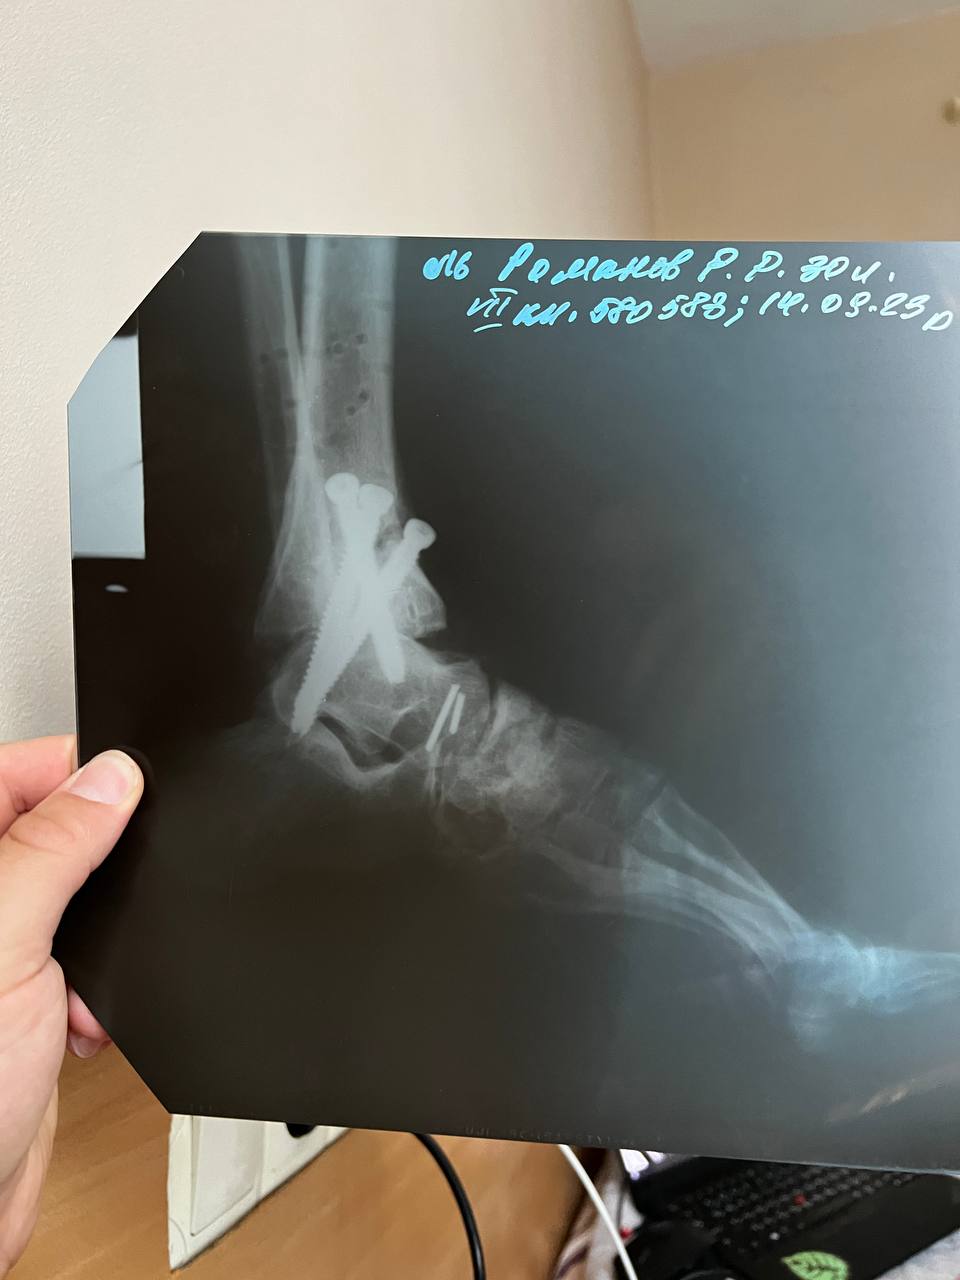

Ruslan had a closed fracture of his left leg, the limb was broken below the knee to the tips of the toes. He underwent four surgeries in more than a year, and now, instead of a joint, there are three large screws. Also, after the injury, he had to stitch up the jaw on both sides.